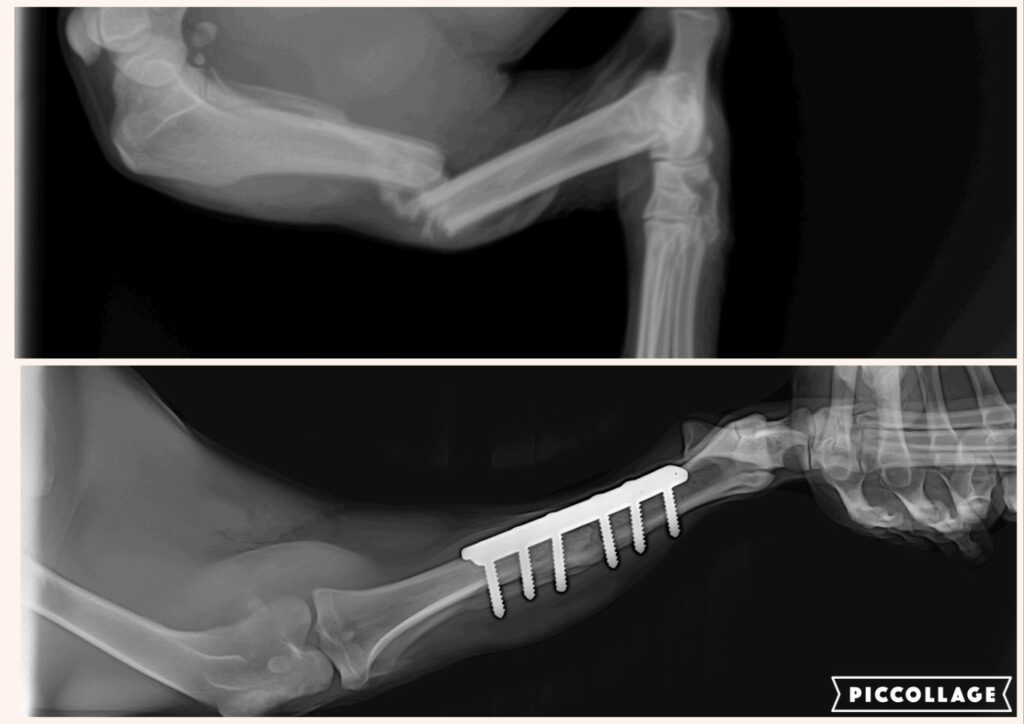

Z praxe

Reálné zákroky a ošetření z naší ordinace.